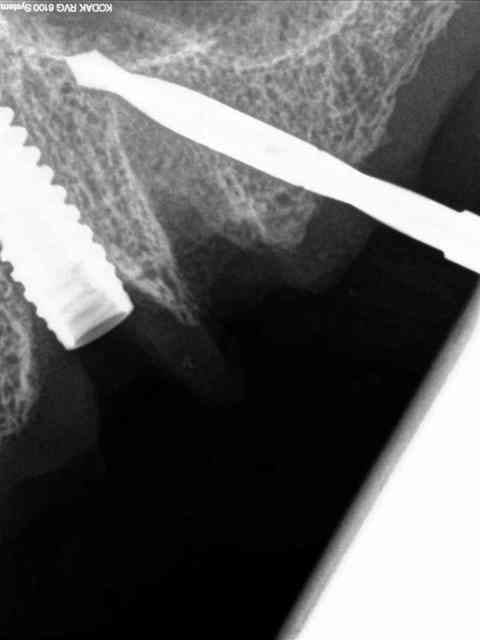

je vous mets les radios per-op.

secteur 1:

à l'aide du guide je détermine la position et l'axe de l'implant.

retrait du guide et contrôle radio puis pose des implants

secteur 2:

on voit bien ici que cette méthode reste suffisamment précise pour longer le sinus sans le pénétrer.

je n'en demande pas d'avantage.

> secteur 2:

> on voit bien ici que cette méthode reste suffisamment précise pour longer le

> sinus sans le pénétrer.

> je n'en demande pas d'avantage.

Cet implant pénètre de 5 à 6 mm dans le sinus.